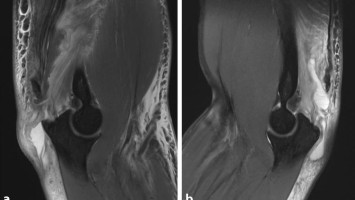

Dorsaler Knieschmerz, aber im nativen MRT war nichts zu sehen

Kein vorheriges Trauma oder Sturzereignis: Eine 40-jährige Patientin stellte sich mit Schmerzen im Bereich des linken Kniegelenkes vor, welche seit ca. 18 Monaten bestanden. Das native MRT reichte nicht für die vollständige Diagnose.